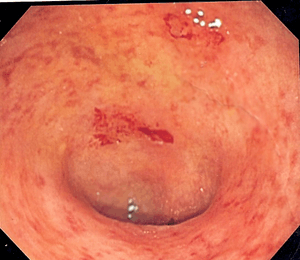

Endoscopic image of a colon affected by ulcerative colitis. The internal surface of the colon is blotchy and broken in places. | |

The best test for diagnosis of ulcerative colitis remains endoscopy. Full colonoscopy to the cecum and entry into the terminal ileum is attempted only if the diagnosis of UC is unclear. Otherwise, a flexible sigmoidoscopy is sufficient to support the diagnosis. The physician may elect to limit the extent of the exam if severe colitis is encountered to minimize the risk of perforation of the colon. Endoscopic findings in ulcerative colitis include the following:

- Loss of the vascular appearance of the colon

- Erythema (or redness of the mucosa) and friability of the mucosa

- Superficial ulceration, which may be confluent, and

- Pseudopolyps.

Ulcerative colitis is usually continuous from the rectum, with the rectum almost universally being involved. There is rarely perianal disease, but cases have been reported. The degree of involvement endoscopically ranges from proctitis or inflammation of the rectum, to left sided colitis, to pancolitis, which is inflammation involving the ascending colon.